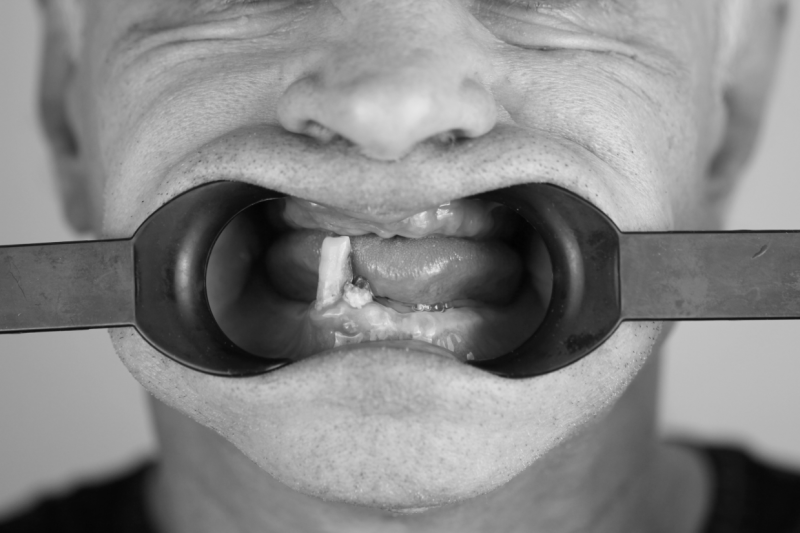

Родионов Артем Геннадьевич принимает в «Сеть стоматологических клиник ЭКСТРОДЕНТ» в Пушкине. Стаж 17 лет. Специализируется на хирургии и имплантологии, по которым клиника оказывает 16 услуг. Имеет 2 работы до/после в портфолио. Квалификация специалиста подтверждена 34 лицензиями, сертификатами и наградами.

2 работы в портфолио